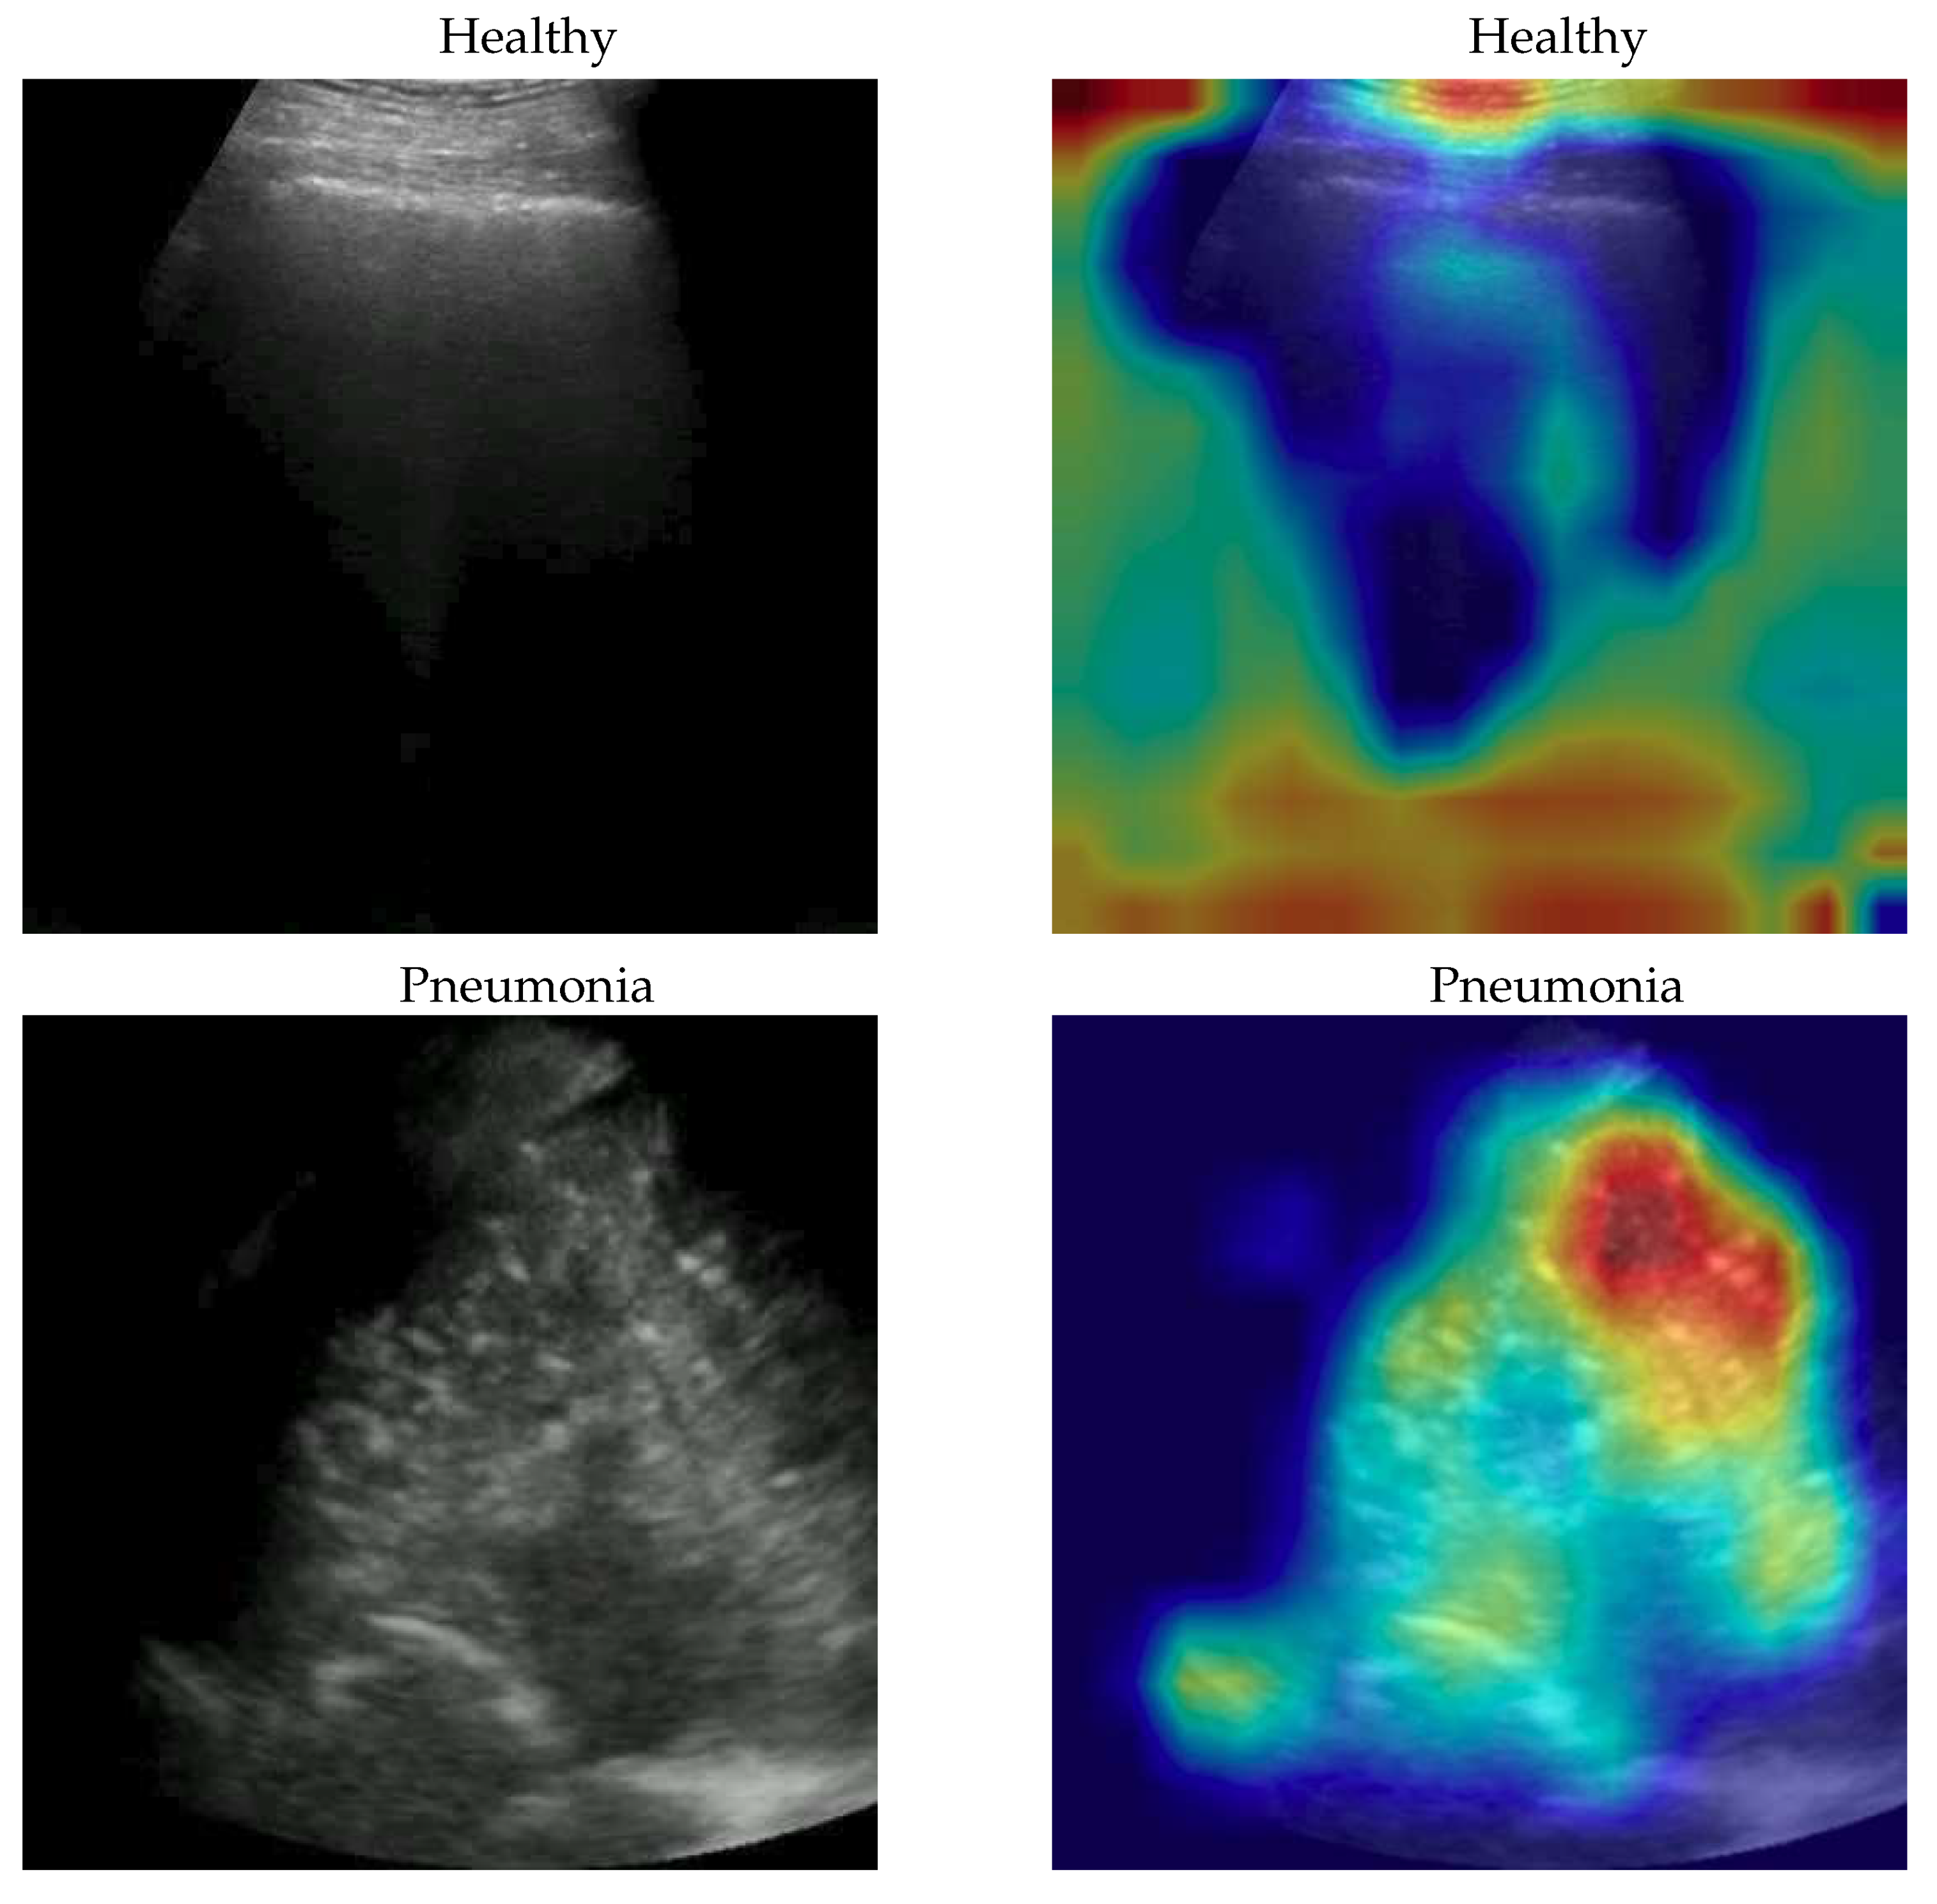

The dataset used for this task is, to our knowledge, the largest publicly available LUS (Lung UltraSound) dataset1, comprising ultrasound videos and images from 261 different patients among 41 different sources. The data have been collected, cleaned and reviewed by medical experts. In particular, for the sake of this work, we used the frame-based version when the frames of each video are considered. In Table 1 data distribution is described and some examples for each class are shown in Figure 1. More details about the whole dataset (e.g. patient distribution, acquisition technique, sources) are described both in the article [25] and in the GitHub repository of the project.

Figure 1. some COVID-19 (first row), Pneumonia (second row) and Healthy (third row) samples from the dataset. As can be seen the images, even among the same class, are very heterogeneous, and there is no kind of bias (e.g. pattern, color).